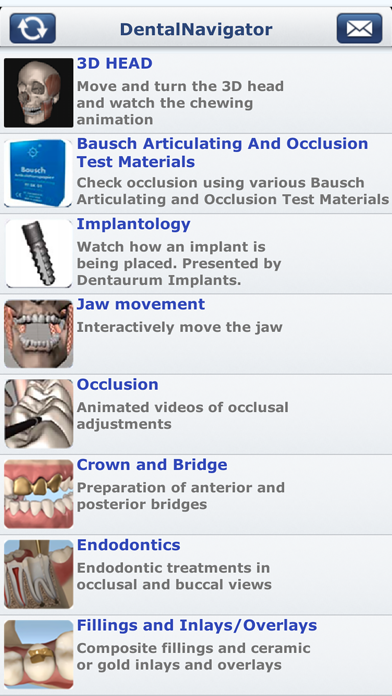

Скриншоты